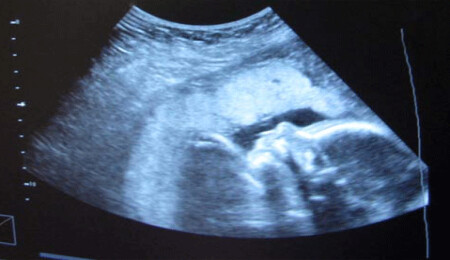

Rum tarafında genç çiftlerin kısırlık sorunu çektiği, her 5 çiftten 1'inin çocuk sahibi olamadığı bildirildi.

Simerini'nin haberine göre Rum tarafında faaliyet gösteren jinekoloji uzmanları bundan 20 yıl önce kısırlık sorununun her 8 çiftten 1'inde görülürken bugün bu oranın 1/5'e yükseldiğine dikkat çekti ve gelecek yıllarda bu oranın daha da büyüyeceği öngörüsünde bulundu.

Kısırlık sorunu nedeniyle genç çiftlerin yoğun olarak tüp bebek yöntemine başvurduğu kaydedilen haberde, tüp bebek meselesinde yasal bir düzenleme yapılmadığını ve tüp bebek merkezlerinin uygulamaları açısından değil sadece özel klinikler yasası uyarınca, kalite açısından denetlendiğini yazdı.